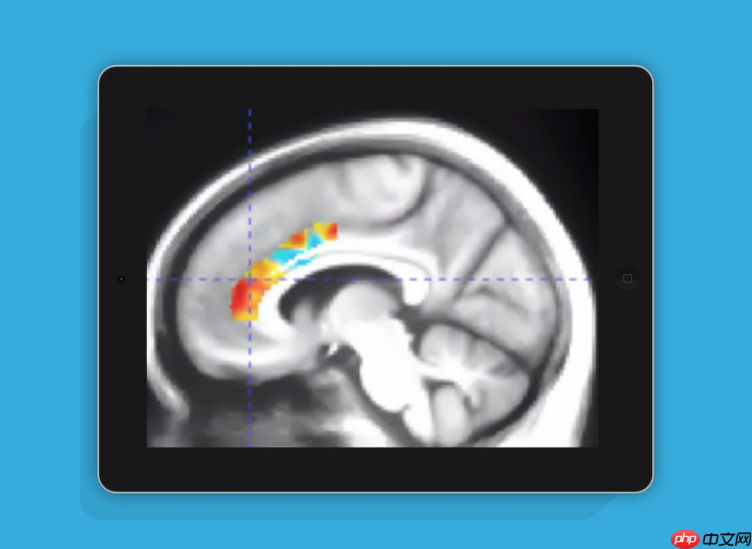

如今,玩游戏早已不再被视为荒废学业或事业的“头号敌人”。根据美国研究机构最新发布的一项调查成果显示,老年人只要坚持玩10周的大脑训练类游戏,其认知功能的改善效果相当于逆转了10年的脑部老化进程。

研究共招募了92名年长参与者,平均年龄为71.9岁,平均接受教育年限达16.5年。经过持续数月的实验干预,结果显示:连续进行10周特定大脑训练游戏的老年人,在认知功能方面表现出显著提升,其大脑功能状态相当于年轻了十年。